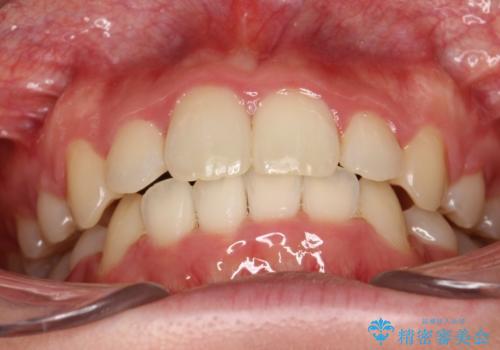

患者様が装置を早期に除去したいという希望もあり、少々下の前歯のがたつきが残った状態で矯正を終了しました。

全体的ながたつきがなくなり、見た目の印象がよくなりました。